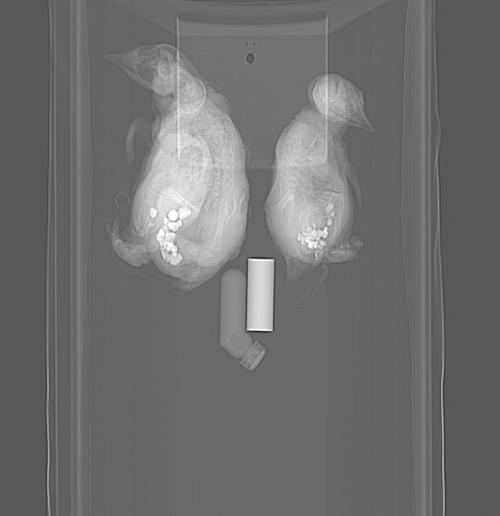

Calling all penguin experts! What’s up with this? Is that really how much gastrolith (stomach stone; near bottom of image) volume a penguin carries (answer after some literature reading: maybe yes!), or did a museum curator stick rocks up its bum? It seems very caudal in position, and this is consistent with other animals I’ve seen (some below). A paper on this phenomenon and potential role in ballast is here. Another here.

Young juvenile. Nice pose, and lots of anatomy is shown. And check it out- gastroliths?!? In such a young animal– is it even feeding yet? (presumably straight after hatching) And they are relatively big pebbles, too! If I noticed this 5 years ago, it would have been a nice paper to report- first recognition of gastroliths in penguin chicks seems to have been then. Indeed, that study observed some chicks intentionally swallowing stones.